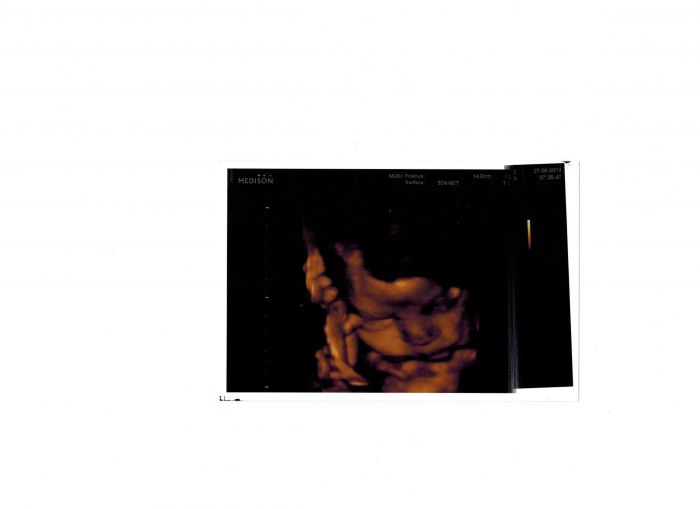

tak tady je ,nosánek nakřivo nemáme

to jen tiskárna tiskla nakřivo v ordinaci